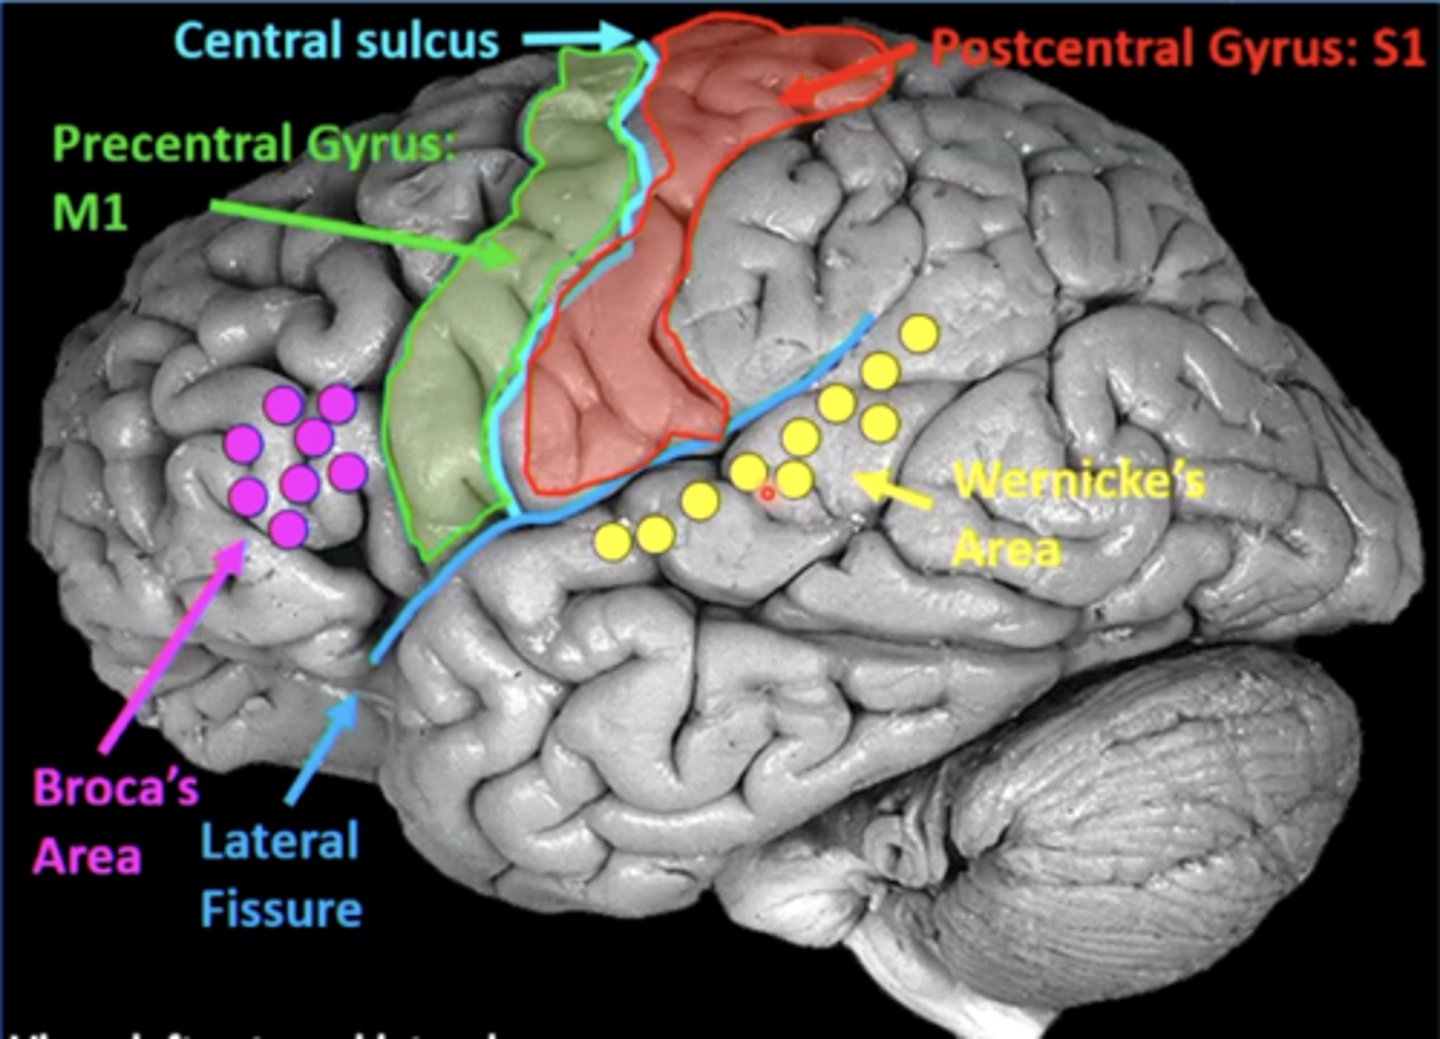

list the cortical region and cerebral lobe of the somatic motor system/primary motor cortex:

cortical region:

precentral gyrus

cerebral lobe: frontal (M1)

list the cortical region and cerebral lobe of the somatosensory system/primary sensory cortex:

cortical region:

postcentral gyrus

cerebral lobe: parietal (S1)

list the cortical region and cerebral lobe of the speech/language system:

cortical region:

Broca's and Wernicke's areas

cerebral lobe: frontal (Broca's) and temporal (Wernicke's)

Broca's and Wernicke's areas are located on the (left/right) hemisphere of the brain in most people

left

a good guess to where the language centers are is based on your dominant hand (right hand dominant --> language centers will be in the left hemisphere)

what is Broca's area?

area in the frontal lobe responsible for language production (speaking, writing, signing)

a lesion in Broca's area could result in what?

Broca's aphasia

results in slow, labored speech, agrammatism (lacking correct grammar), and anomia (inability to name objects)

understanding is good, finding/creating the words is difficult

what is Wernicke's area?

area in the temporal lobe responsible for language comprehension (speech, written language, sign language)

a lesion in Wernicke's area can result in what?

Wernicke's aphasia

person can produce fluent speech/language, but it is meaningless ("word salad")

language production is there, it just makes no sense

what is the arcuate fasciculus?

an axonal pathway that connects Wernicke's area to Broca's area

cell bodies are in Wernicke's area, and axons synapse in Broca's area